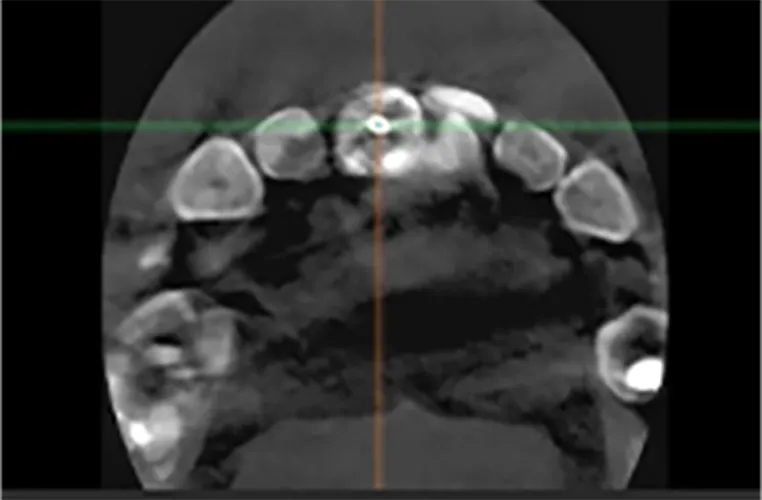

検査・診断

CT撮影や口腔内の検査を行い、骨の状態・咬み合わせなどを詳しく診断します。

この結果をもとに、インプラントの本数や治療法(オーバーデンチャーかオールオンX)を決定します。